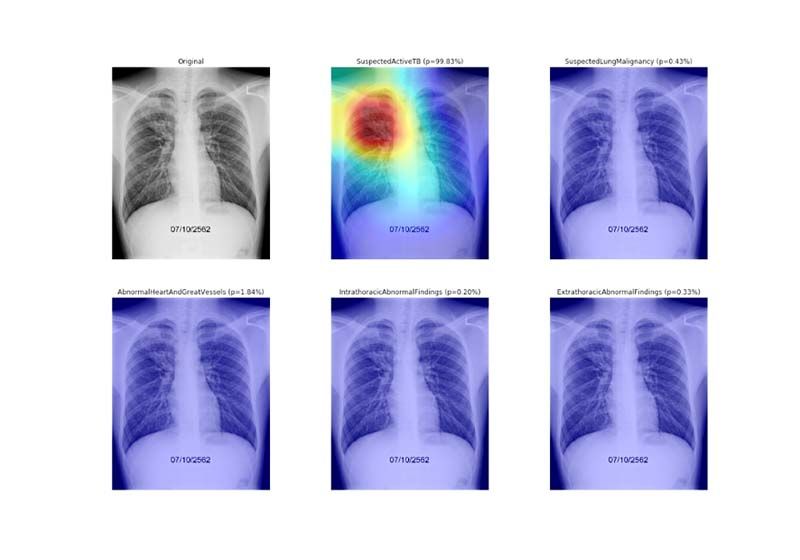

รองศาสตราจารย์ ดร.จาตุรงค์ ตันติบัณฑิต อาจารย์ประจำภาควิชาวิศวกรรมไฟฟ้าและคอมพิวเตอร์ คณะวิศวกรรมศาสตร์ มหาวิทยาลัยธรรมศาสตร์ (TSE) เปิดเผยว่าความอยู่รอดของประชากรโลกจากการระบาดของโรคโควิด-19 กลายเป็นวาระสำคัญด้านสาธารณสุขของทั่วโลก ซึ่งในระหว่างที่หลายประเทศรวมถึงประเทศไทยกำลังเร่งรณรงค์เพื่อสร้างภูมิคุ้มกันหมู่ด้วยการฉีดวัคซีน ธรรมศาสตร์ได้มีส่วนร่วมโดยนำนวัตกรรมปัญญาประดิษฐ์ทางการแพทย์“เอไอเชสต์ฟอร์ออล” (AIChest4All)ไปช่วยคัดกรองความผิดปกติภาวะปอดอักเสบในผู้ป่วยโควิด-19 ซึ่งทำได้อย่างแม่นยำกว่า 90 เปอร์เซ็นต์ รู้ผลทันที ส่งผลให้สามารถคัดกรองผู้ป่วยที่มีความเสี่ยง ในกรณีที่มีอาการปอดอักเสบได้ทันท่วงที ซึ่งก่อนหน้าที่จะพัฒนาเอไอดังกล่าว การวินิจฉัยความผิดปกติจากภาพถ่ายเอกซเรย์ (X-Ray) จะใช้การแปรผลจะใช้เวลาเกือบ 5 นาทีต่อภาพ ในขณะที่ “เอไอเชสต์ฟอร์ออล” (AIChest4All) ใช้เวลาประมวลผลได้อย่างรวดเร็ว เพียงแค่ 1-2 วินาทีต่อภาพ อำนวยความสะดวกในการทำงานของทีมแพทย์อย่างยิ่ง และได้นำไปใช้งานจริงในโรงพยาบาลของรัฐทั่วประเทศ โดยไม่เสียค่าใช้จ่ายแล้ว

“เอไอเชสต์ฟอร์ออล” (AI Chest4All) เป็นเอไอ ได้ร่วมพัฒนา กับกรมการแพทย์ กระทรวงสาธารณสุข เพื่อช่วยจำแนกกลุ่มอาการและความรุนแรงจากภาพถ่ายเอกซเรย์ (X-ray) ทรวงอก ได้อย่างถูกต้องแม่นยำและรวดเร็ว อาทิ มะเร็งปอด วัณโรค ความผิดปกติของหัวใจ ความผิดปกติภายในทรวงอก และปอดอักเสบ ทำงานบนระบบคลาวด์ (Cloud) ที่ทำหน้าที่เชื่อมต่อโยงข้อมูลภาพฟิล์มเอกซเรย์ (X-Ray)จากโรงพยาบาลของรัฐในสังกัดกรมการแพทย์ กระทรวงสาธารณสุขที่มีอยู่หลายร้อยแห่งทั่วประเทศ เพื่อนำมาประมวลผล และส่งผลที่ได้กลับไปยังทีมแพทย์จากต้นทางในทันที สามารถรู้ผลเรียลไทม์